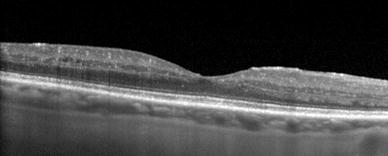

Near-infrared reflectance image (left) and blue light fundus autofluorescent image (right) demonstrating drusen and geographic atrophy in a patient with dry age-related macular degeneration (AMD)

In general, blue- and green-light FAF imaging has proven valuable for assessment of patients with AMD, in particular those patients with geographic atrophy [34, 40, 41]. In such patients, areas of atrophy appear hypoautofluorescent due to the confluent loss of RPE cells (and thus loss of the fluorescent signal generated from their lipofuscin granules). The boundaries of these atrophic areas are often more clearly visualized on FAF imaging than on conventional fundus photography (Fig. 2) [42]. A number of studies have also suggested that the autofluorescent patterns seen in the areas surrounding foci of geographic atrophy can be predictive of the rate of disease progression [40, 43].